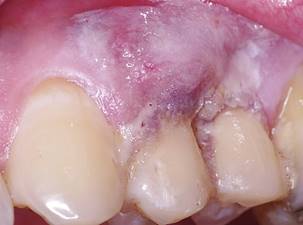

A 43-year-old male, ASA I, patient sought treatment for gingival retraction and hypersensitivity in tooth 24. At clinical examination, a gingival recession type (RT) 1 (according to Cairo`s classification system8), 2 mm. in length, was diagnosed (Fig. 1). Probing depth (PD) and clinical attachment level (CAL) were 1 mm. and 4 mm., respectively (Table 1). The characteristics of the gingival margin, gingival thickness and dental morphology were compatible with a thick biotype. Scaling and hygiene instructions were performed one week before surgery. The patient was informed of the risks and benefits and signed an informed consent.

The root coverage procedure was performed using an envelope technique5, aiming to fully cover the exposed root area, reestablishing the natural gingival contour and treating the hypersensitivity.